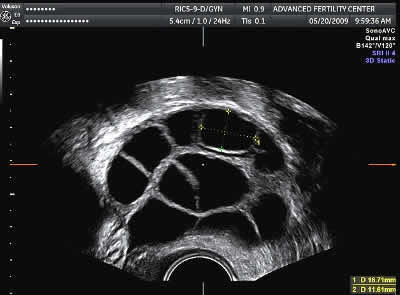

Also, because I know you’re wondering what an ovary with follicles on it looks like:

(No, this is not my ovary)